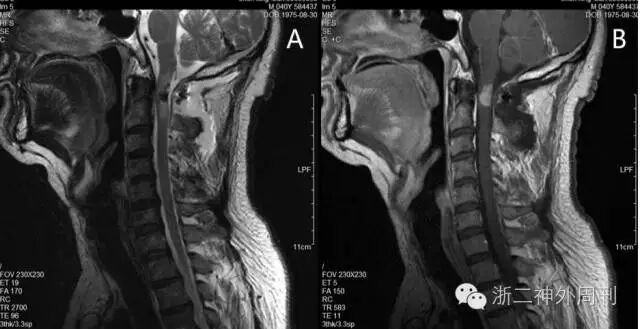

术后患者左上肢麻木减轻,无肢体肌力异常。查MRI显示肿瘤部分切除(图4)。

图4. 术后T2加权相及增强相均提示肿瘤残留,但突出脊髓部分已切除。